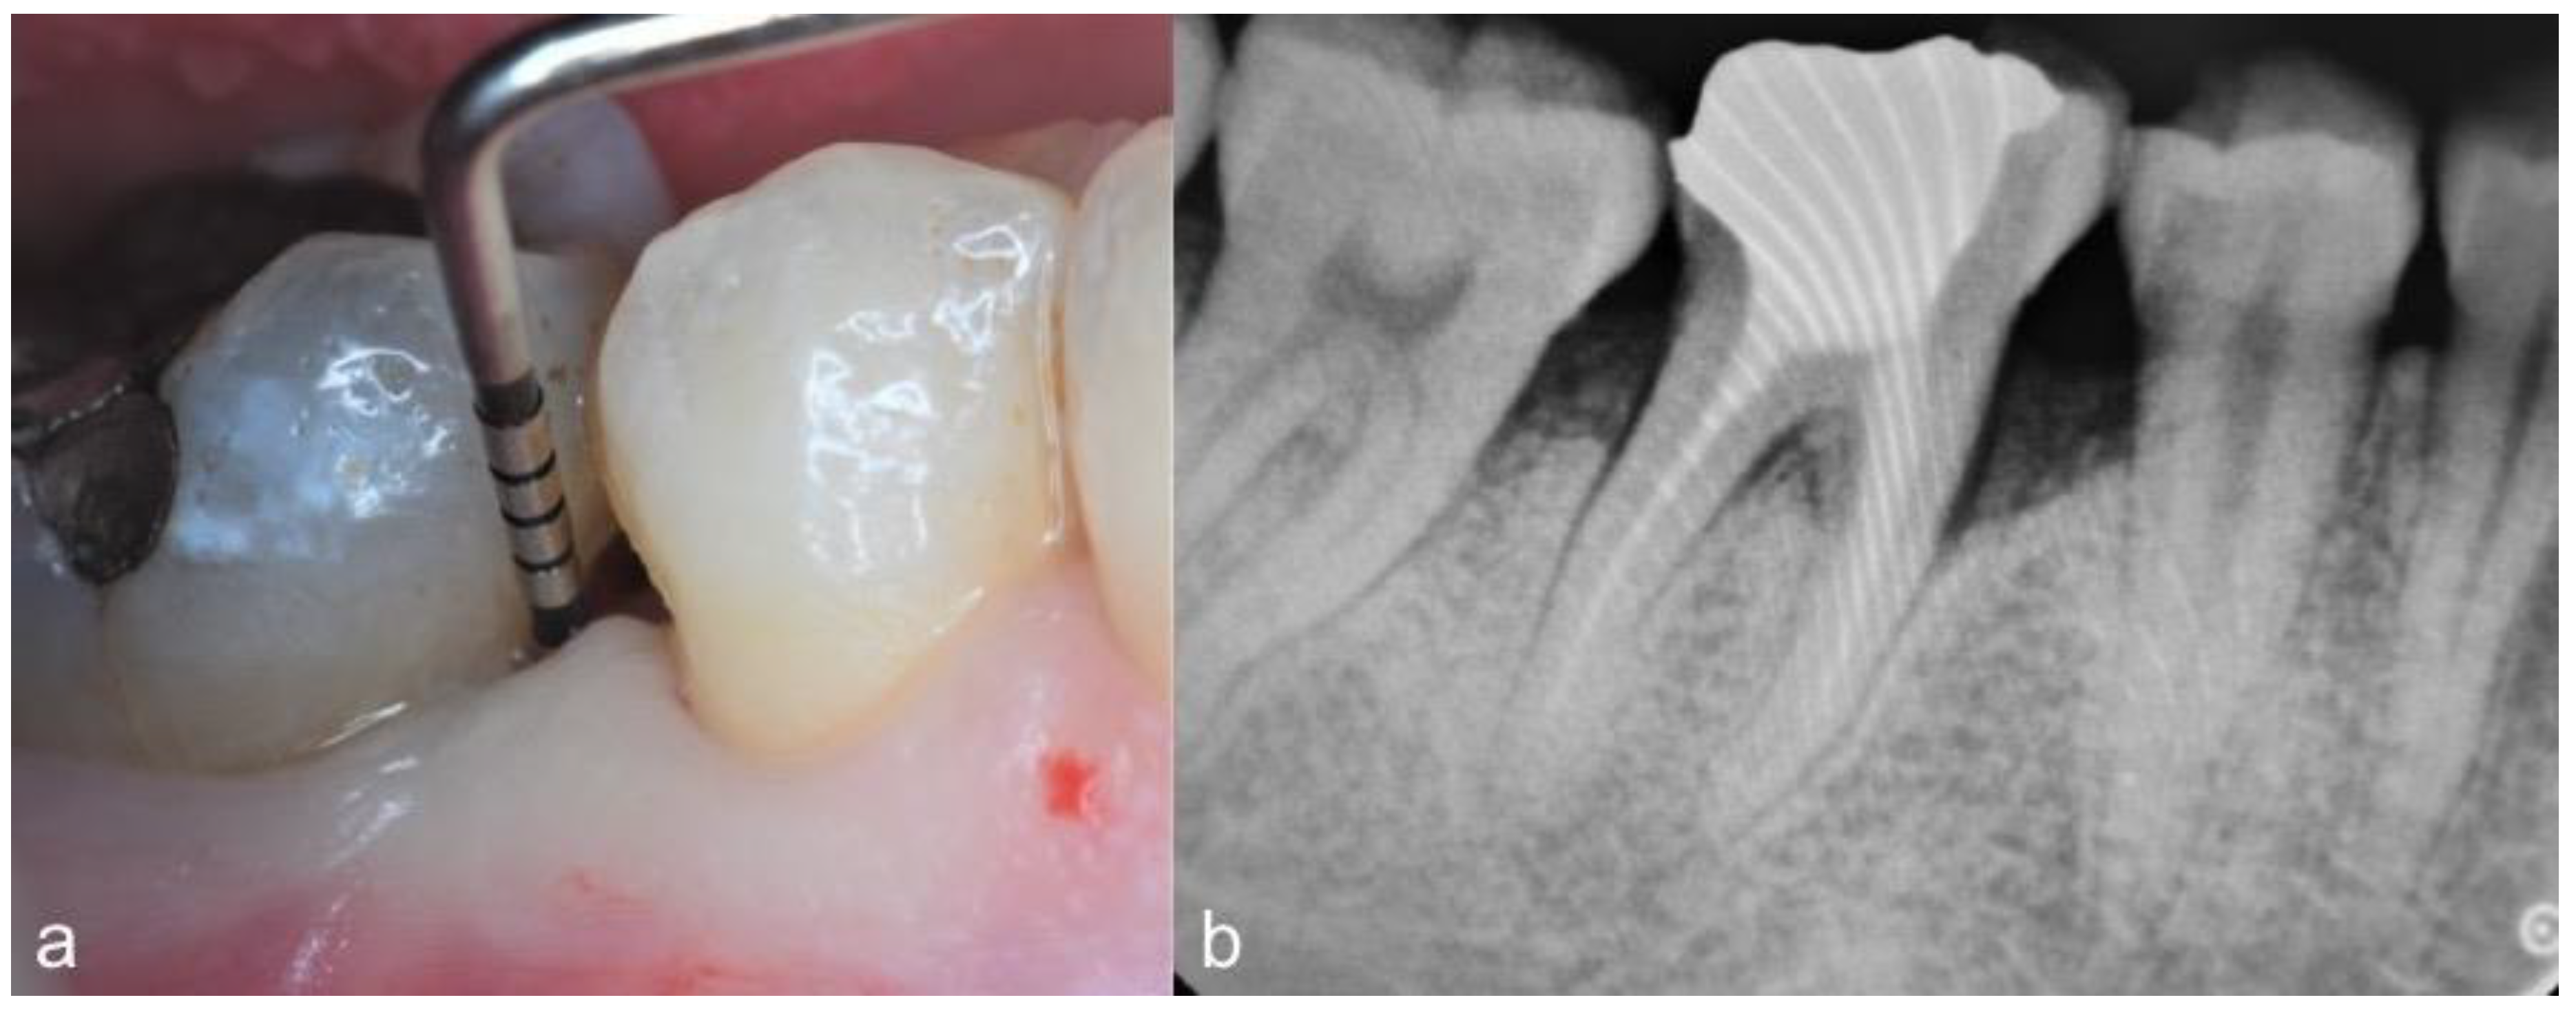

2.2. Clinical Findings

2.3. Therapeutic Intervention